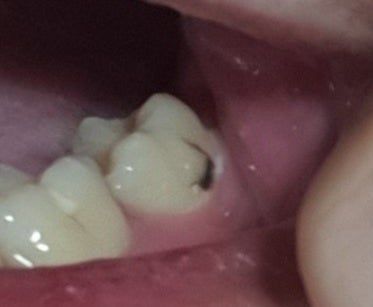

사진상으로는 충치의 범위가 커서 신경치료 및 추가적인 치료의 가능성도 있어보입니다.

충치가 겉표면에만 살짝 생긴 것이라면 레진 등의 치료를 할 수 있습니다.

레진 등의 치료는 보통 8만 원에서 12만 원 정도에 비용이 들어가게 됩니다 하지만 충치의 깊이가 깊다면 레진 이외에 보철 치료를 해야 할 수도 있습니다.

안녕하세요 치과의사 김철진입니다. 엑스레이를 찍어봐야 알겟지만 간단한 충치라면 저부위만 제거하고 레진치료를 하면되겟지만, 다른부위까지 충치가 잇다면 인레이 또는 신경치료를 하셔야될수도 있습니다.

신경치료를 들어갈지가 중요한 판단점입니다. 다만, 증상이 없어서 표면의 충치일 가능성도 있습니다.

현재 충치가 어느정도 진행이 된 것으로 보이며, 정확한사항은 충치의 깊이를 확인해야 치료금액 산정이 가능합니다. 따라서 치과에 방문하여 우선 진료를 받길 권하며, 레진으로 떼우는 경우에는 20-30만원선이나, 크라운 치료시에는 금액이 더 발생할수 있습니다.

정확한 것은 x-ray 등의 촬영이 필요합니다. x-ray 등의 촬영으로 해당 부위의 충치 정도를 파악해야 합니다. 육안으로 보았을 때는 신경치료를 동반한 크라운을 해야할 가능성이 높아 보이나 정확한 판단을 위해서 가까운 치과 방문을 권해드립니다.